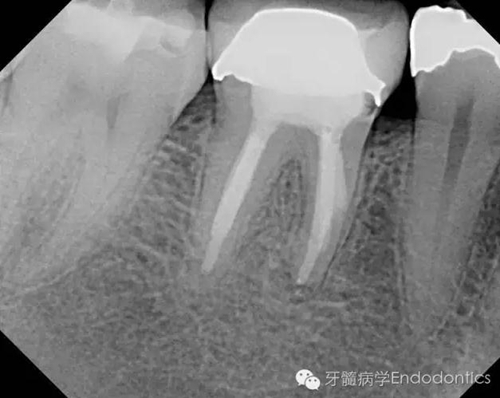

患者因右下第一前磨牙劇烈疼痛、腫脹來診,自訴2年前該牙行根管治療,突發(fā)劇痛。X線示患牙已行根管治療并超填。患牙診斷為已行根管治療合并急性根尖周膿腫。一些牙醫(yī)和牙髓病專科可能會直接采取根尖手術(shù)治療患牙,而我認(rèn)為手術(shù)是最終手段,尤其對于該病例。

圖1.術(shù)前X線片(a)